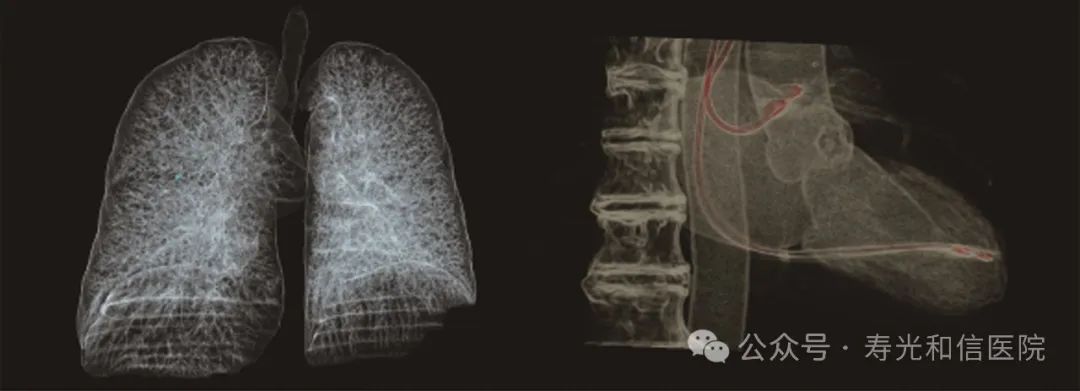

微剂量体检筛查

采用液态金属轴承技术的超大热容量球管,结合独有的低千伏、低毫安成像模式,联影640层CT可实现肺部、冠脉等全身各部位大扫描通量、微辐射剂量的体检筛查。